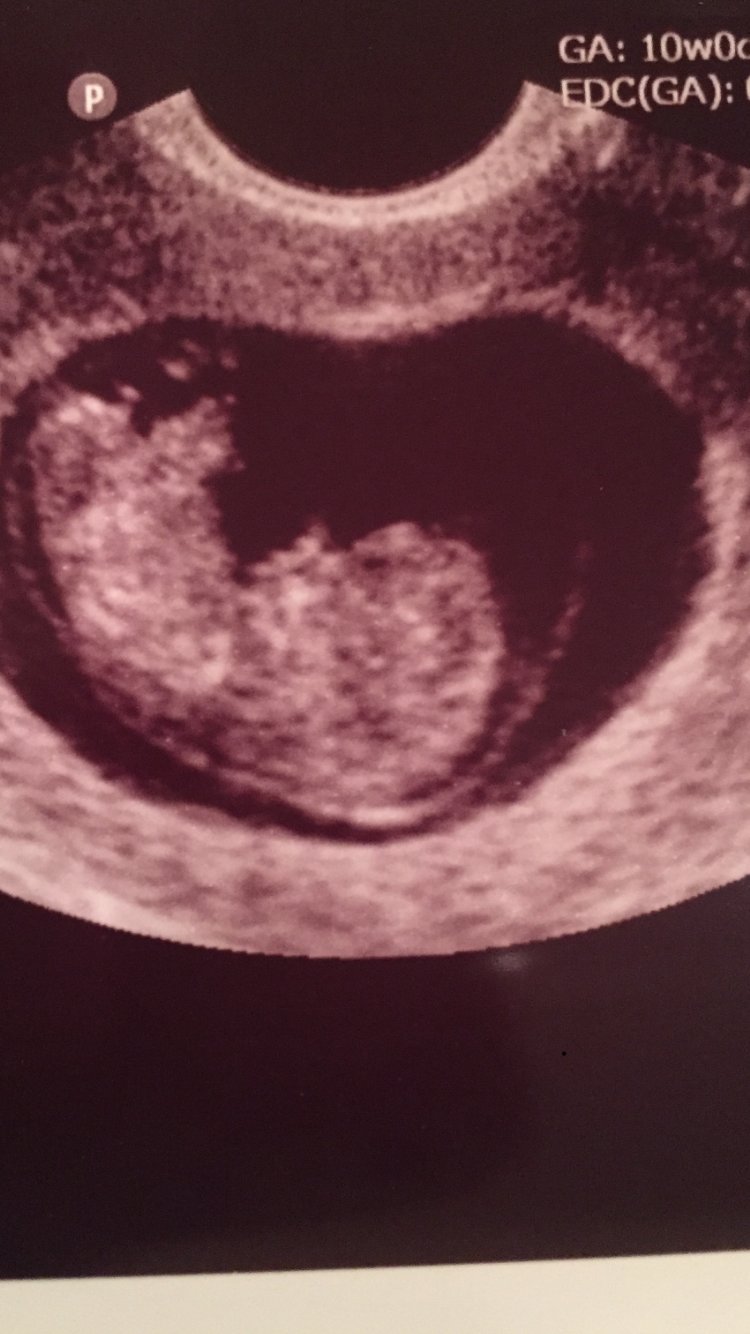

Guess who had her first OB visit - yep this girl!! I too had to find a new OB but I loved her. She spent time going thru my history and made me feel really comfortable. Only issue she’s one of 2 docs in the office but the only one who delivers babies so we’ll see how that goes. I don’t go back for another 4 weeks which seems like an eternity. The baby is growing right on track and everything looks good. I couldn’t be happier.

@rainbows2018 what a cute US!!! Glad u like ur dr that's awesome!! With my high risk dr doing tests I'm still seeing my nugget every 2 weeks im not ready for the full 4weeks!

Awe love the US pic. Bump had logged me out for days. I feel you on still being nervous. We’re 14+ weeks and I still can’t post on social media. We sent our Christmas announcement cards to extended family last week but for some reason I still can’t do it. We have another Appt next week so maybe after that. Hope all you ladies are doing well. I can’t believe the holidays are so close now.

What a great pic @rainbow2018 glad you liked your ob. @Holls214 I don't plan on posting on social media until probably July I'm too nervous to put myself out there like that. Thanks for the advice @Hopeful_mom I will def bring up concerns in 4 weeks when I see her again.

Thanks ladies!! It finally looks like a baby so that makes me feel good. No big announcements for us either but we have a family Xmas party on the 23rd and I’m trying to decide whether or not to tell everyone. I think I’m still at a point where people may think I’m fat and not necessarily PG but we shall see. I bought a ton of maternity clothes from motherhood maternity online - they had some good sales around thanksgiving. I’m loving the maternity leggings and dresses. I know it’s still early but right now comfort trumps everything.